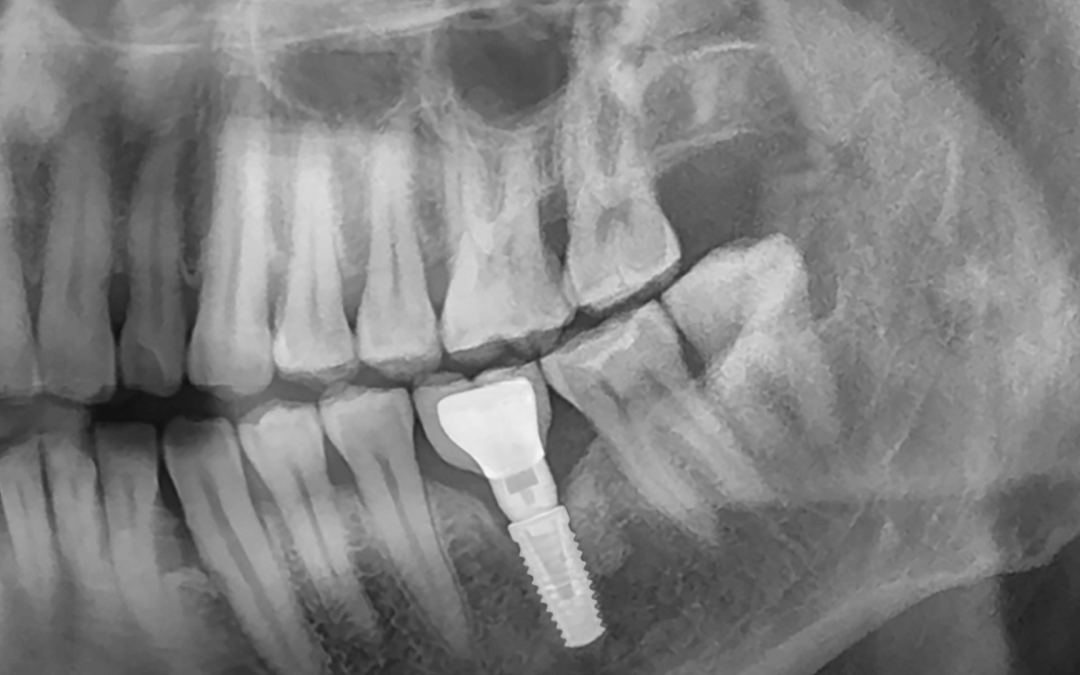

Implantes dentales en mayores de 65: ¿Es seguro? ¿Vale la pena recuperar la sonrisa?

Implantes dentales en Lanzarote: Todo lo que necesitas saber antes de decidirte BEJA Dental, tu clínica Dental en Lanzarote Los implantes dentales en Costa Teguise (Lanzarote), son el método de sustitución de dientes con más éxito y fiabilidad de la actualidad. Siendo...

Implantes dentales en Lanzarote